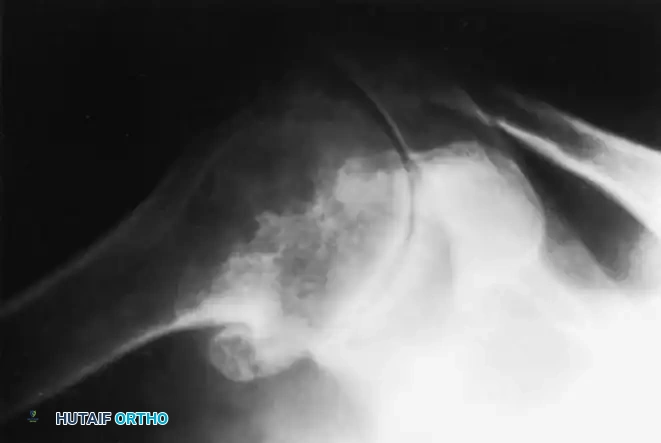

Preoperative Imaging:

Standard radiographs must include a true anteroposterior (Grashey), axillary lateral, and scapular Y view. A non-contrast CT scan is mandatory for evaluating glenoid bone stock, version, and morphology (utilizing the Walch classification for posterior wear).